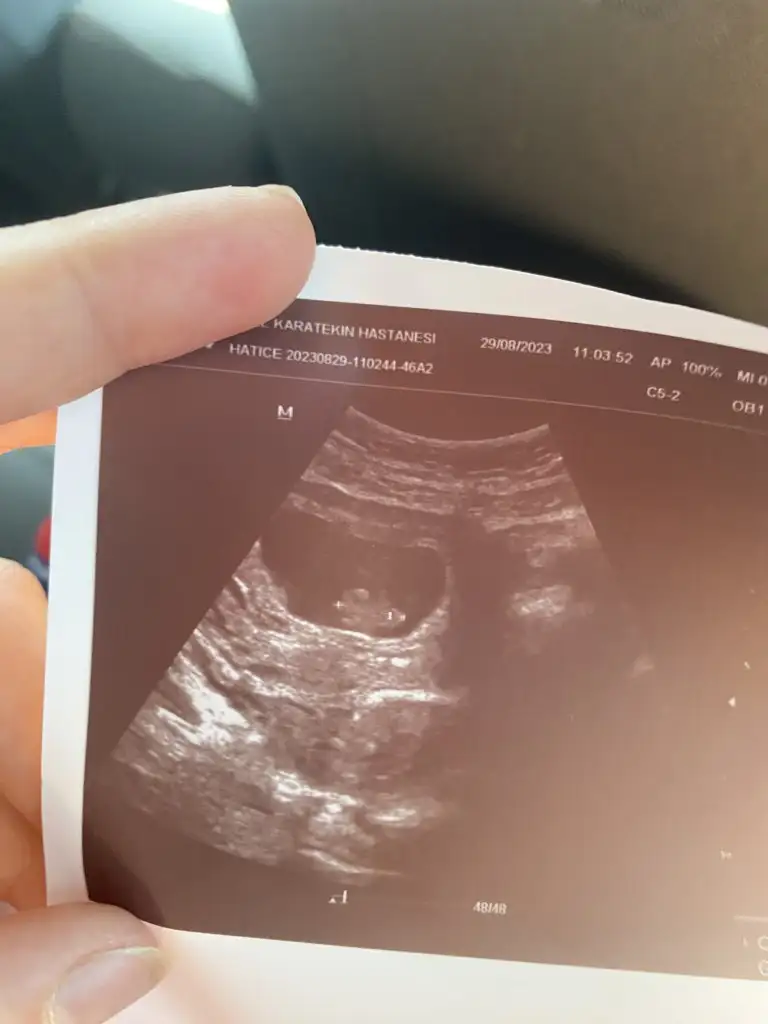

Kıza benziyor. Fakat birkaç hafta sonra tekrar atarsanız nub kısmına bakarız öyle tekrar tahmin ederim. Sağlıkla gelsin bebecik inşallah.Banada tahminde bulunur musunuz 2 nci gebeligim ilk gebeligim kız sezeryan dogum yapyorum suan 11 haftalk hamileyim

Banada bir tahminde bulunur musunuz lütfenKıza benziyor. Fakat birkaç hafta sonra tekrar atarsanız nub kısmına bakarız öyle tekrar tahmin ederim. Sağlıkla gelsin bebecik inşallah.

Bu bebeğin nubu belli değil ama yüzde üzerinden değerlendirme yapacak olsam %60 kız derdimBanada bir tahminde bulunur musunuz lütfen

Ya gercekten mi çok sevinirim kız olursa gerçekten, belli olunca size kesin yazacağım, gönlümden geçen kız ama tabiki öncelikle sağlıklı olması derimBu bebeğin nubu belli değil ama yüzde üzerinden değerlendirme yapacak olsam %60 kız derdim